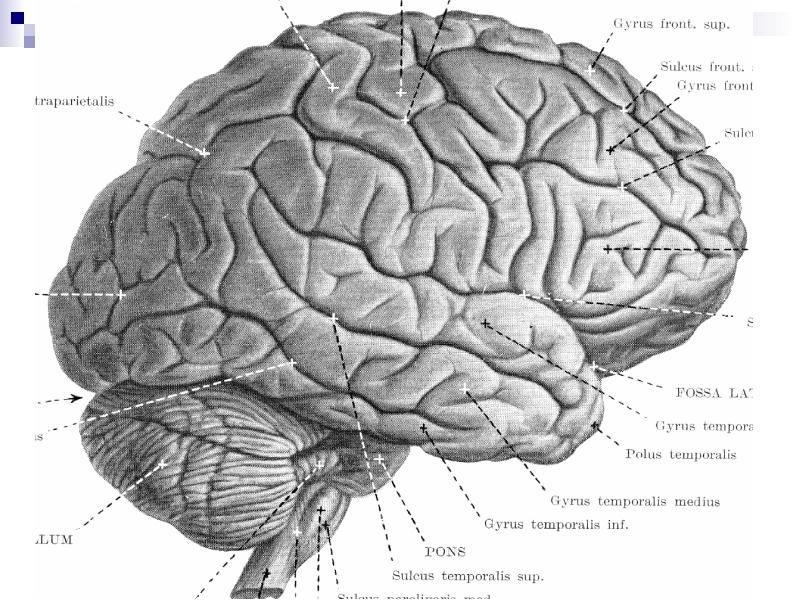

Анатомические снимки верхнелатеральной поверхности головного мозга